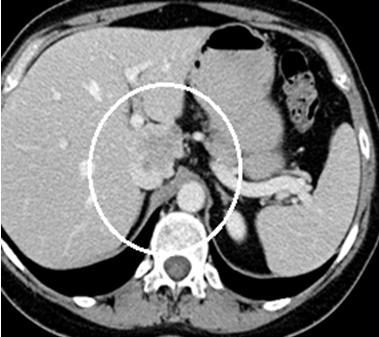

Pacienta a fost o femeie de 50 de ani. Aceasta a fost diagnosticată cu o tumoare masivă hepatică, preponderent S I, cu invazia venei cave inferioare porțiune retrohepatică și prezența simptomelor pozitive caracteristice sindromului de ocluzie a venei cave inferioare. La internare, femeia acuza dureri moderate în regiunea lombară, edeme și pastozitate a membrelor inferioare. Diagnosticul preoperator a fost stabilit pe baza investigatii CT cu contrastare in regim angiografic. Până acum așa amplasare a tumorii a fost considerată inoperabilă. Potrivit prof. univer., dr. Adrian Hotineanu, până acum acești pacienți erau refuzați pentru tratament radical și primeau doar îngrijiri paliative fără efect, care duceau inevitabil la deces. Medicul a menţionat că “toate acestea pot fi depășite doar prin tratament radical, prin rezecția hepatică cu tumoare și rezecția venei magistrale. Numai această metodă este potențial curativă și poate oferi vindecare”.

Astfel, pentru a salva viaţa pacientei, doctorii au rezecat o parte de ficat, purtător de tumoare, au mobilizat şi lanțuit porțiunea retrohepatică a venei cave inferioare. Ulterior s-a rezecat în bloc cu tumoare, care s-a înlocuit cu proteză vasculară. Medicii spun că perioada postoperatorie decurge favorabil. La moment pacienta se simte bine şi se pregatește pentru externare.